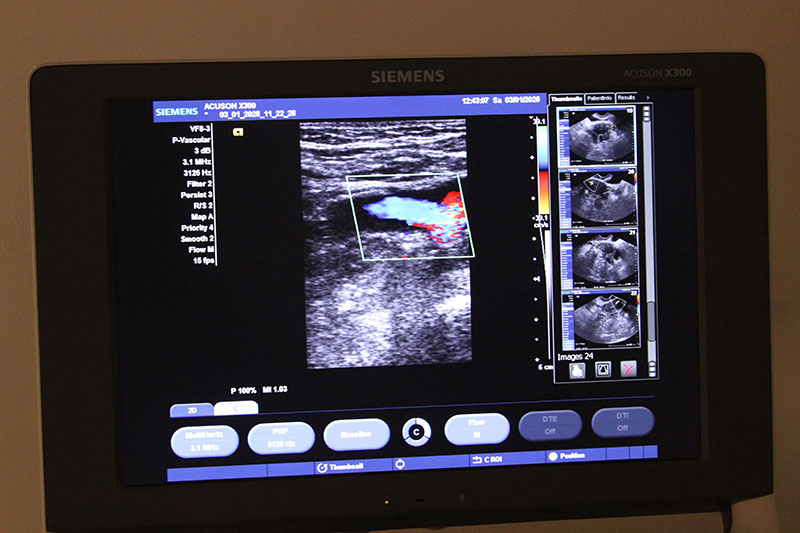

Ультразвуковое исследование щитовидной железы (УЗИ) – это безопасная и информативная процедура, которая позволяет визуализировать ткани органа, обнаружить узловые образования или признаки воспаления на ранней стадии. Процедура безболезненна, исключает радиационное воздействие и занимает не больше 30 минут.